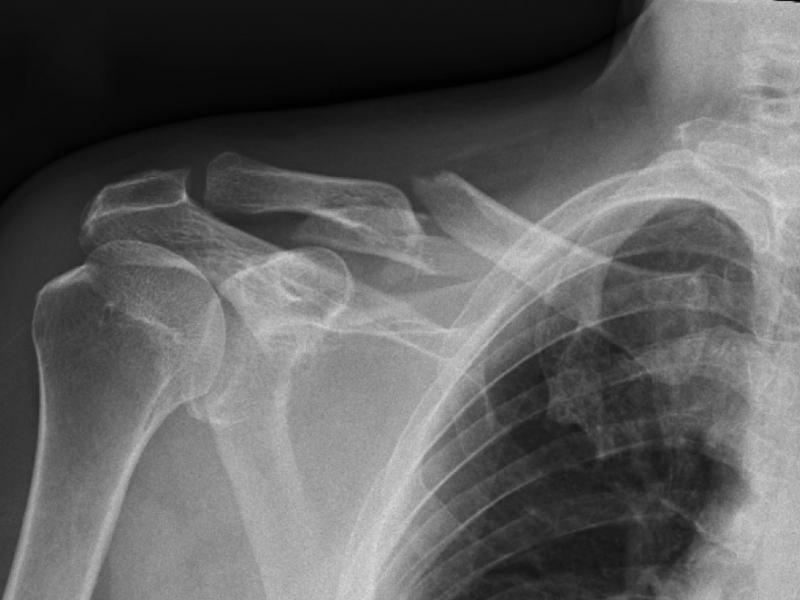

A 60 yo male slipped on ice and fell onto his right shoulder